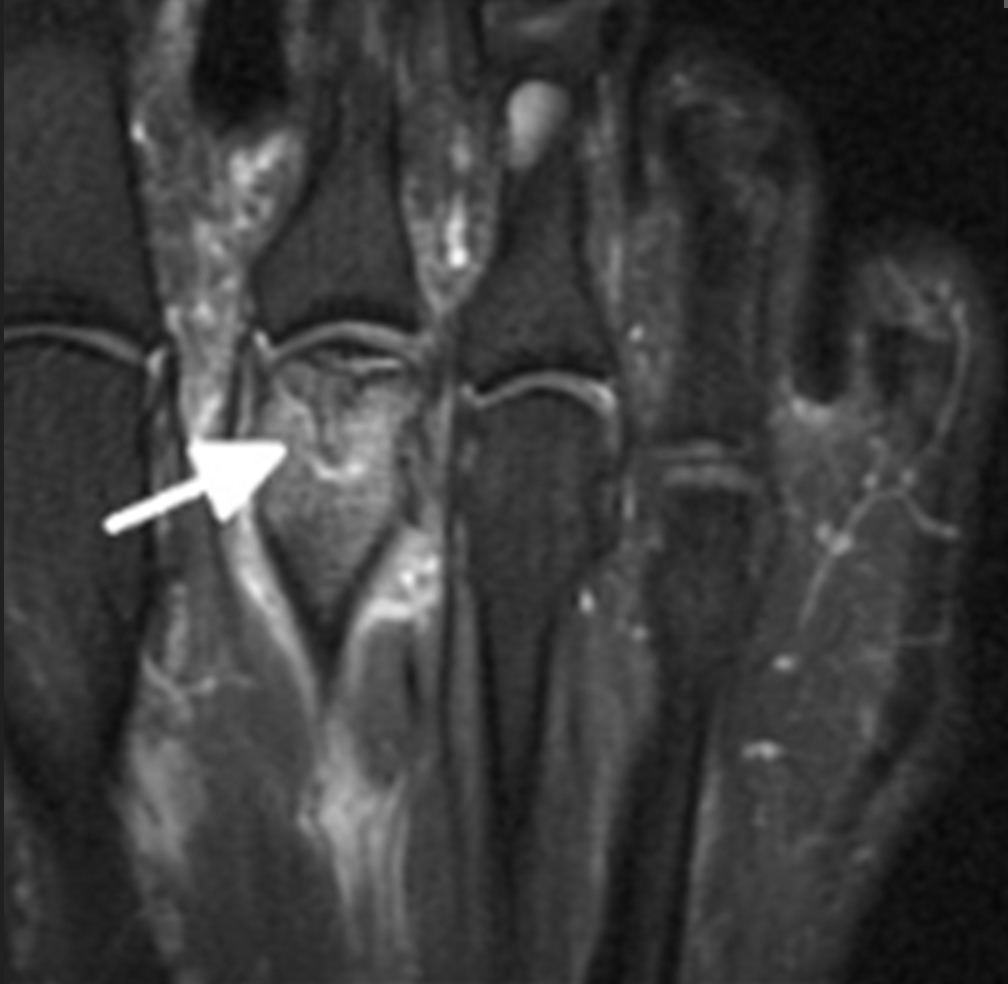

MRI scan

An MRI scan may be used when:

- Symptoms are present but X-rays appear normal

- Early-stage disease is suspected

- There is uncertainty about the diagnosis

- Surgical planning is required

MRI can detect:

- Early bone changes before collapse occurs

- Bone marrow oedema

- Cartilage damage

- The extent of joint involvement

This makes MRI particularly useful in early Freiberg’s disease.

MRI is good at showing active and latent disease, especially in the early stages where X-rays are sometimes not useful